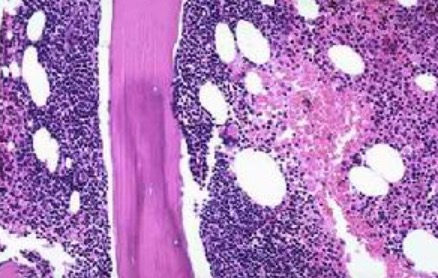

- 淋巴癌早期症状是什么

在临床方面淋巴癌疾病是个很常见恶性肿瘤疾病,并且大多数的人听到淋巴癌之后,都会不自觉的与死神挂钩,基本上不会给自己留下什么希望,所以说做到发现早期的症状时,早期进行治疗是非常重要的,那么淋巴癌早期症状是什么呢?